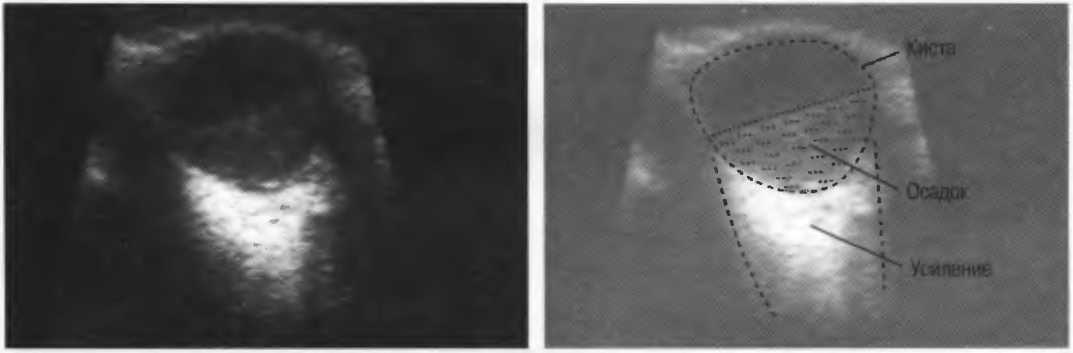

Киста |

Жидкость (содержащая структура, объемное образование) с тонкой стенкой. Простая киста характеризуется анэхогенным (эхосвободным) содержимым. наличием сильного усиления по задней стенке и усилением кзади от кисты. Гистологически киста может быть доброкачественной и злокачественной. |

Кисты

Киста, как правило, визуализируется в виде анэхогенной зоны, при этом структуры, расположенные за кистой, обычно усилены: полость кисты анэхогенна, поскольку в ней нет структур с различным акустическим сопротивлением. В результате того что жидкость не поглощает ультразвук в такой же степени, что и ткань, эхо-сигналы от расположенных позади кисты структур гиперкомпенсированы сканером и выглядят усиленными — появляется эффект усиления задней стенки (рис. 14а,б).

Киста определяется в виде анэхогенной зоны с усилением по задней стенке. Если в кисте есть внутренние зхоструктуры, то они могут быть реальными или являться артефактами.

Рис. 14а. Заполненная жидкостью киста: полость кисты анзхогенна, имеется усиление задней стенки.

Рис.14б. Данная киста яичника имеет толстые стенки и внутренний осадок, создающий внутреннюю эхоструктуру, перемещающуюся при перемене положения тела пациента.

Структура, наподобие содержащей чистую жидкость кисты, визуализируется как анэхогенная зона. Стенки кисты отражают ультразвуковые сигналы под углом, и информация не поступает назад в трансдьюсер. В результате этого появляются боковые тени, но сзади кисты имеется усиление эхосигналов (усиление задней стенки) (рис. 15).

Рис. 15а. Киста печени: жидкость внутри чистая, анэхогенная. Стенки кисты отражают ультразвук под углом от датчика, вызывая появление боковых теней.

Рис. 15б. Плодные яйца при анэмбрионии: две жидкостьсодержащие структуры с задним усилением и латеральными тенями.

Артефакты могут определяться в любой кистозной структуре (такой, например, как мочевой пузырь или желчный пузырь) и чаще определяются ближе кпереди, становясь менее выраженными на глубине. Они исчезают или меняют свой характер при изменении положения датчика. Но истинные структуры в кисте, такие как перегородки, сохраняют свое местоположение независимо от положения датчика. Истинные отражения имеют место при наличии сгустка крови, гноя, некротической взвеси, и все это чаще визуализируется по задней стенке: если эти структуры не фиксированы к стенке, они изменяют свое положение при перемене положения тела пациента (рис. 16).

Осадок в кисте может флотировать, формируя уровень, изменяющий свое положение при перемещении пациента (рис. 16б,в).

Рис. 16б. Киста с усилением по задней стенке, латеральными тенями и осадком в полости.

Рис. 16в. Этот же пациент, что и на рис. 16б. Сканирование осуществляется в разных положениях больного. Уровень, создаваемый осадком, смещается.